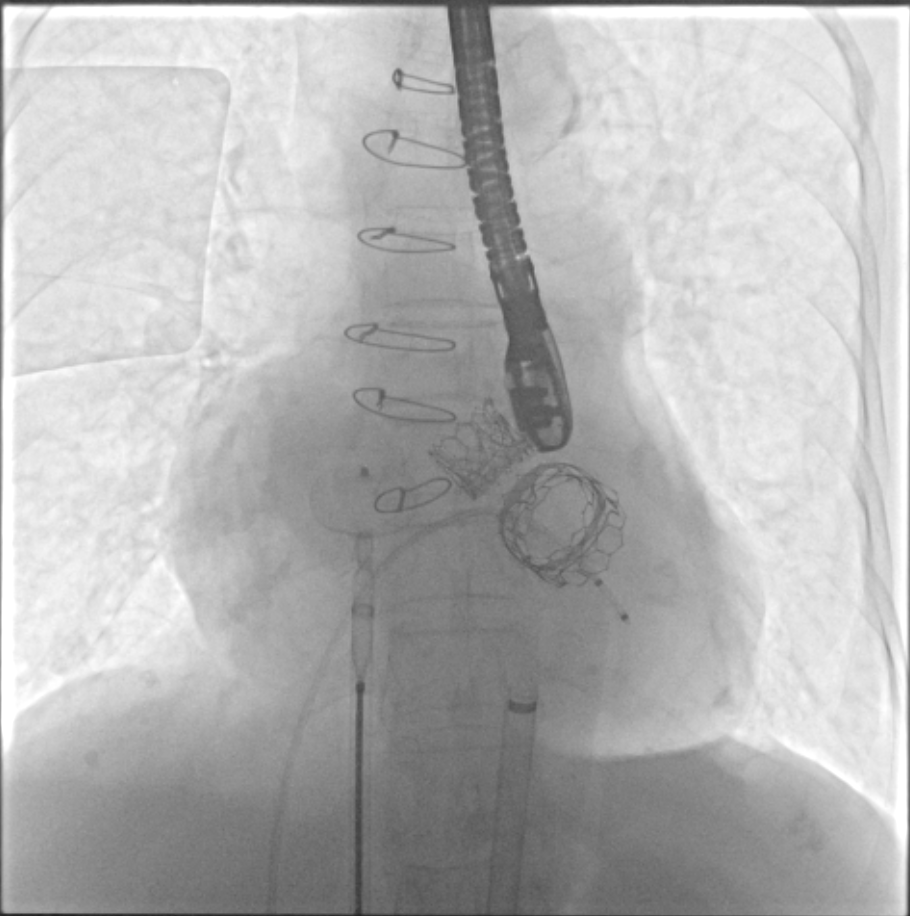

TMVR 术后房间隔封堵